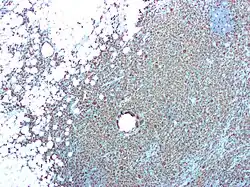

Eine CD68-Immunfärbung wird bei der Diagnose der malignen Histiozytose, beim histiozytären Sarkom und bei Morbus Gaucher eingesetzt.[4][5]